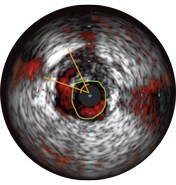

Malapposition is identified by blood behind the stent struts. ChromaFlo imaging colors blood flow red for easy recognition of malapposition and other lumen features.